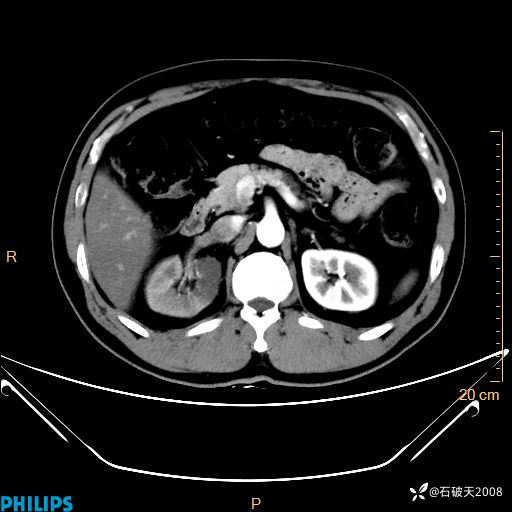

平扫轴位